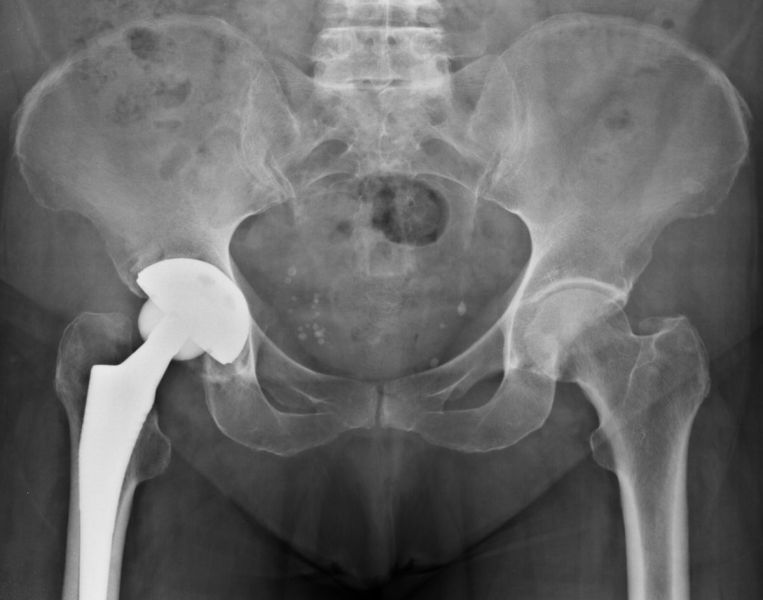

1. Osteoarthritis of both hips but is more severe on the right side.

Treatment: Total hip arthroplasty in a 73-year-old female

I. Anteroposterior x-ray of the pelvis and hips II. One-month post-surgery, anteroposterior x-ray pelvis shows the THA III. One-month post-surgery, lateral x-ray of the right hip showing the exact position of the stem in the femur